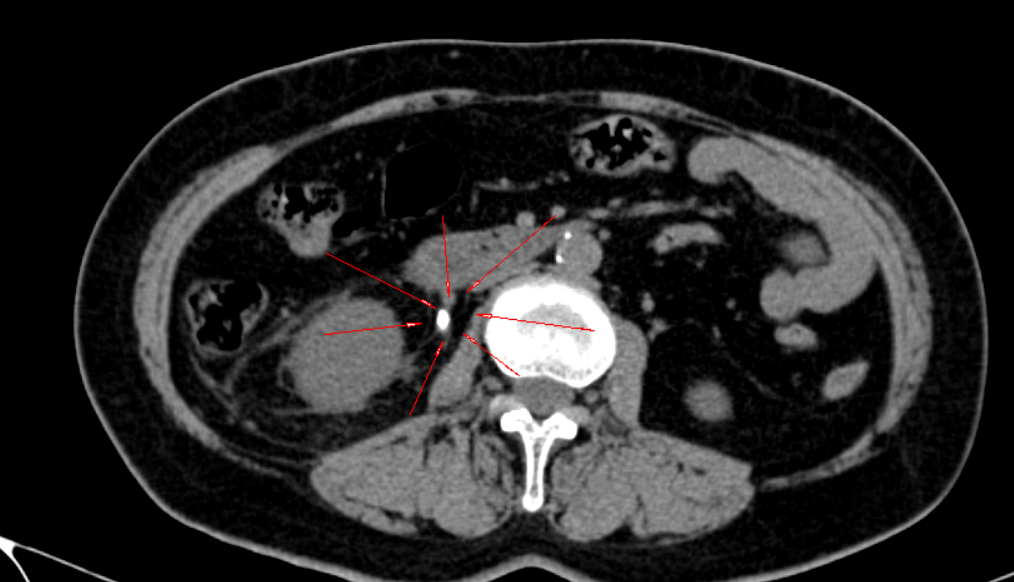

7月7日上午,王女士(化名)因右下腹突发剧痛紧急就诊。怀着焦虑与不安,她到影像科接受腹部CT平扫。检查中,王俊与梁犇共同阅片分析,凭借扎实的专业功底与敏锐洞察,迅速精准锁定病因——右侧输尿管上段结石。这一关键诊断为临床制定治疗方案提供了精准的影像学依据。